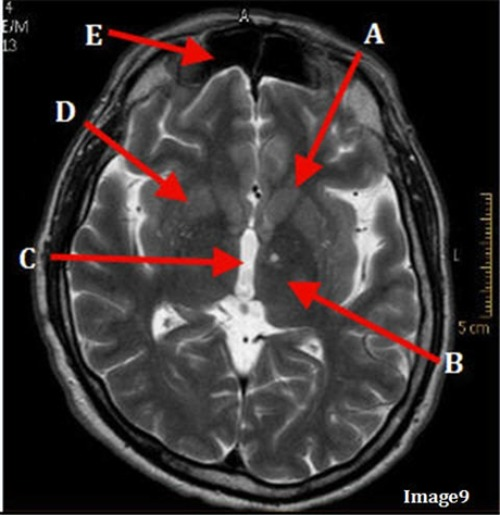

Image 9 is an example of a _____ weighted sequence acquired in the ______ scan plane.

A. T1; Axial

B. T2 FLAIR; sagittal

C. T2; Axial

D. T2; Coronal

Letter E in Image 9 is pointing to:

A. Maxillary sinus

B. Sphenoid sinus

C. Frontal sinus

D. Ethmoid sinus

Letter C in Image 9 is pointing to:

A. Third ventricle

B. Thalamus

C. Lentiform nucleus

D. Caudate nucleus

Letter A in Image 9 is pointing to:

Letter D in Image 9 is pointing to:

Letter B in Image 9 is pointing to: